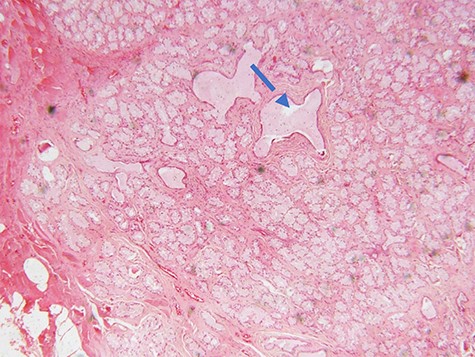

Microscopic examination of the excisional biopsy materials showed a lesion composed of proliferating acinar (Fig. 1) with lining epithelium composed of columnar to cuboidal mucin-secreting cells showing no atypia (Fig. 2). The lesion was divided by fibrous septae to form lobules (Fig. 3). There was a focal area that was showing element of moderate dysplastic changes with element of obliterating tubules, increased hyperchromasia and moderate pleomorphism (Fig. 4). The ratio of duct-to-acini was maintained. Sparse chronic inflammatory infiltrate composed of mainly lymphocytes was present. Neither mitoses nor necrosis were present. The surgical margins were free of the lesion. This confirmed the histopathological diagnosis of Bartholin’s gland hyperplasia with dysplastic changes. After a period of 1 month she was called for clinical evaluation. Healing of the surgical scar was complete and she reported no discomfort or dyspareunia during sexual intercourse.

photomicrograph of haematoxylin and eosin (H and E) stained tissue section showing a focus of dysplastic changes. The areas with dysplastic changes show proliferating hyperchromatic and moderately pleomorphic cells causing obliteration of the lumen of the tubules (dotted arrow) (×200 magnification)